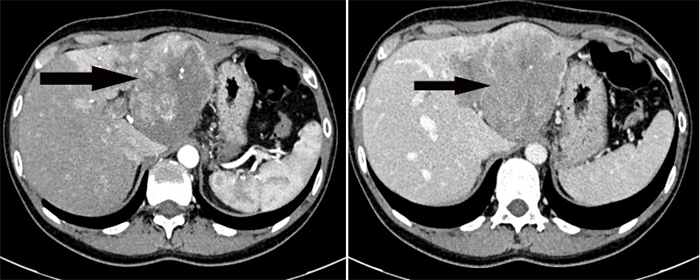

患者1,33岁女性,因“腹部胀痛不适半月”入院,经CT检查提示肝左叶巨大占位性病变,伴门静脉左支癌栓形成,考虑肝恶性肿瘤。